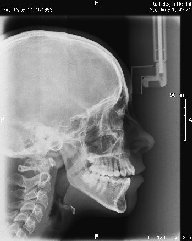

Algunos ejemplos de imágenes digitales

Pulse en las imágenes para ver la ampliación

14lado